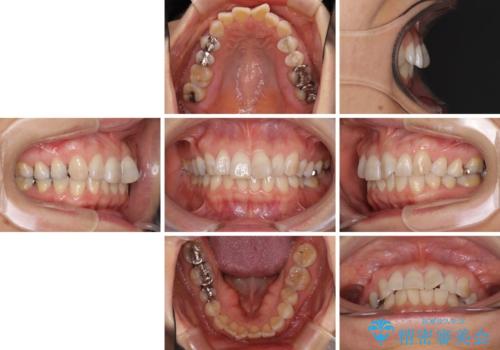

インビザラインは、ワイヤー矯正と異なり、患者様がしっかりと使うということが治療成功の絶対必須条件となります。

十分な装着時間が達成できず、治療途中で後戻りを起こすことがあり、インビザラインの有効期限内に終了させることができませんでした。

ワイヤー矯正や別システムのマウスピース矯正を利用することで、何とか終了させることができました。